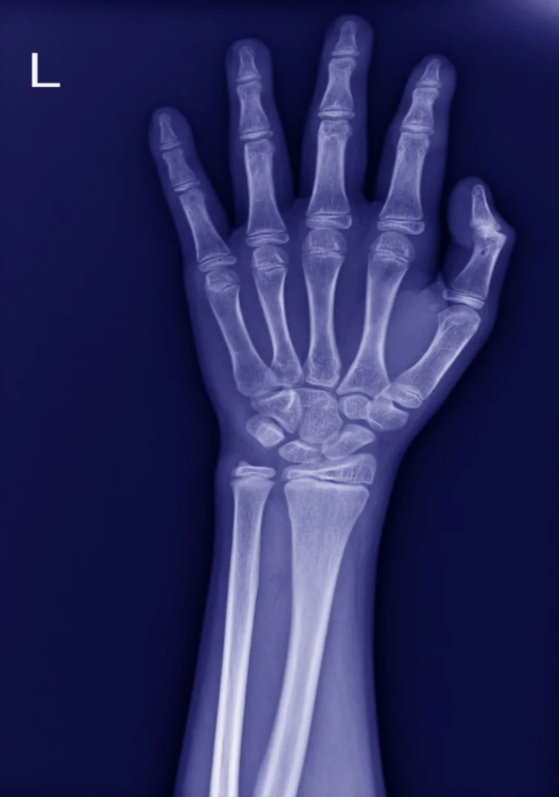

A buckle fracture, also called a torus fracture, results from compression. Instead of cracking, the bone develops a small bulge on one side. This type of fracture is stable and does not involve a full break. It frequently occurs in the wrist after a fall onto an outstretched hand and is generally less serious than a greenstick fracture.

Diagnosis is typically made through physical examination and X-rays. A greenstick fracture appears as a break on one side of the bone, while a buckle fracture shows a slight bulging of the outer bone layer.